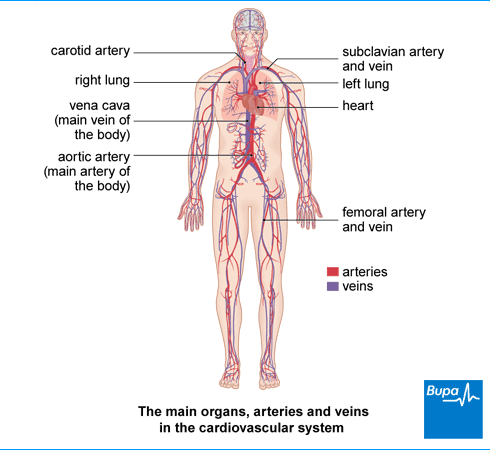

Why Is AB Blood Type So Rare? It’s All About The Red Blood Cells

Mar 25, 2016 – “Blood group A has only A antigens.” Similarly, blood group B has only B antigens, blood group AB has both, and blood group O has neither A nor B antigens on the surface of the red blood cells. These four groups are the most important because they indicate which blood type a patient can safely receive in a transfusion.

AB Positive Blood Type Facts

about Lord Byron arteries OUTPUT messages|

Thrombocytes

AB Positive Blood Type Facts (AB+). 1. Universal Plasma Donor and Universal Red Cell Recipient. The nature of antigens present in the serum determines the …

Blood type – Wikipedia

A blood type is a classification of blood based on the presence and absence of antibodies and …. Therefore, an individual with type AB blood can receive blood from any group (with AB being preferable), but cannot donate blood to any group …

Heme | definition of heme by Medical dictionary

Heme binds and carries oxygen in the red blood cells, releasing it to tissues. Also spelled haeme. See also hemoglobin, porphobilinogen, protoporphyrin.